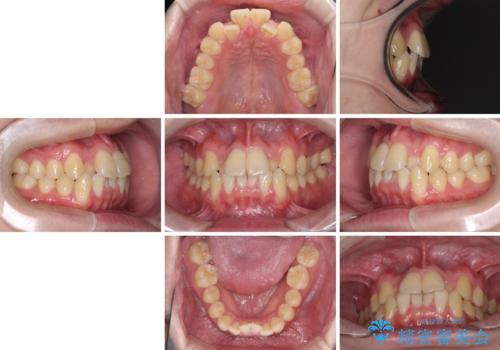

前歯のクロスバイト インビザラインによる矯正治療

- 上下のクロスバイトと前歯のデコボコを気にして来院された患者様です。

インビザラインを用い、IPR(歯と歯の間を削る)と歯列全体を拡大させることで、歯並びを整えていくこととしました。

上下ともに歯列全体を後方に移動させるため、上下の親知らずを抜歯することとしました。

奥に位置していた上の前歯が下の前歯を乗り越える際、奥歯でものを咬むことができず、辛い時期が続きました。